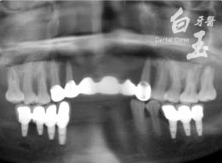

患者全口 X 光

治療前